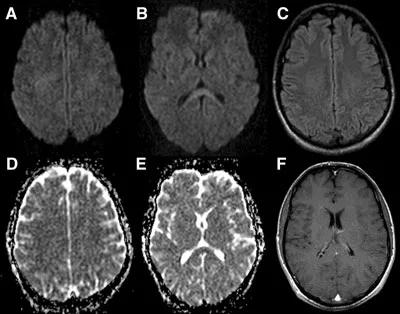

48岁,男性,长期饮酒过量20年,出现出现眩晕,胼胝体、侧脑室周围白质、内囊后肢对称性异常信号,扩散受限,诊断为原发性胼胝体变性急性期。